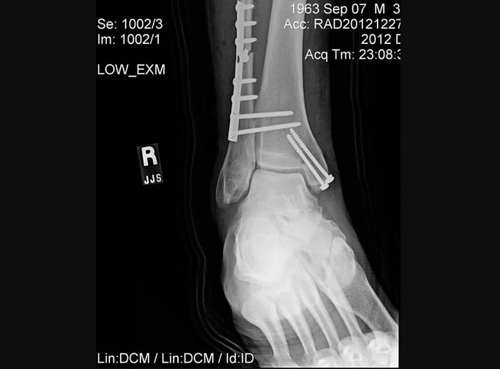

이 병원 최고 의료책임자인 아니시 마하잔 박사는 성명에서 우즈의 오른쪽 다리에서 '분쇄 개방 골절'(Comminuted open fractures)이 발견됐다고 밝혔다.

'분쇄 골절'은 뼈가 여러 곳에서 산산조각이 났다는 의미이고, '개방 골절'은 뼈가 제 위치를 벗어나 피부를 찢고 나온 상황을 말한다.

의료진은 철심을 박아 무릎 아래 두 개의 긴 뼈인 정강이뼈와 종아리뼈를 고정했다.

또 발과 발목뼈는 수술용 나사와 핀으로 안정시켰다.

나사는 일반적으로 골절된 뼈를 접합하는 데 사용되고, 핀은 탈구됐을 수 있는 관절을 바로 잡는 데 쓰인다.